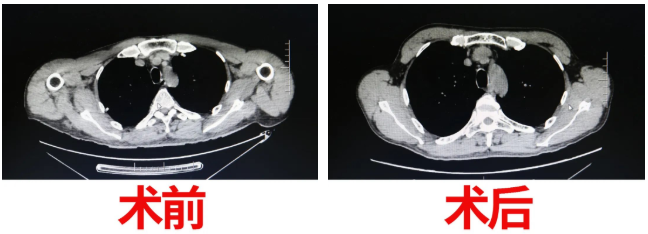

術(shù)前,胸外科醫(yī)護(hù)人員多次對(duì)該患者進(jìn)行心理疏導(dǎo),解除患者疑慮。經(jīng)過(guò)了縝密的術(shù)前準(zhǔn)備后,于5月27日,在麻醉科及手術(shù)室的完美配合下,周鋼院長(zhǎng)對(duì)該患者成功的實(shí)施了手術(shù)治療。由于患者胸腺瘤與心臟大血管侵及生長(zhǎng)粘連緊密,術(shù)中手術(shù)難度極大,經(jīng)驗(yàn)豐富的周院長(zhǎng)僅用了不到1小時(shí)的時(shí)間,經(jīng)劍突下2cm小切口及雙側(cè)肋弓下三個(gè)“鑰匙孔”,成功分離并完整切除胸腺瘤,完成了該例經(jīng)劍突下入路?微創(chuàng)技術(shù)難度含量較高的手術(shù)。

重癥肌無(wú)力的手術(shù)治療效果,是伴隨著患者的恢復(fù)慢慢改善的。在胸外科醫(yī)護(hù)團(tuán)隊(duì)精心、周到的護(hù)理下,術(shù)后,患者眼肌無(wú)力癥狀立即消失,術(shù)前視物模糊、全身乏力等癥狀也得到了改善?;颊唛_(kāi)心的向病友們炫耀:“真沒(méi)想到,這么大的手術(shù),刀口才這么小,現(xiàn)在的技術(shù)真是好呀!”患者更是對(duì)醫(yī)護(hù)人員無(wú)微不至的照護(hù)所感動(dòng)。